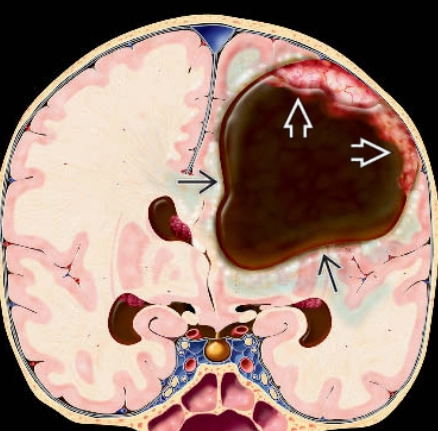

U nguyên bào thần kinh đệm (Glioblastoma- GBM)